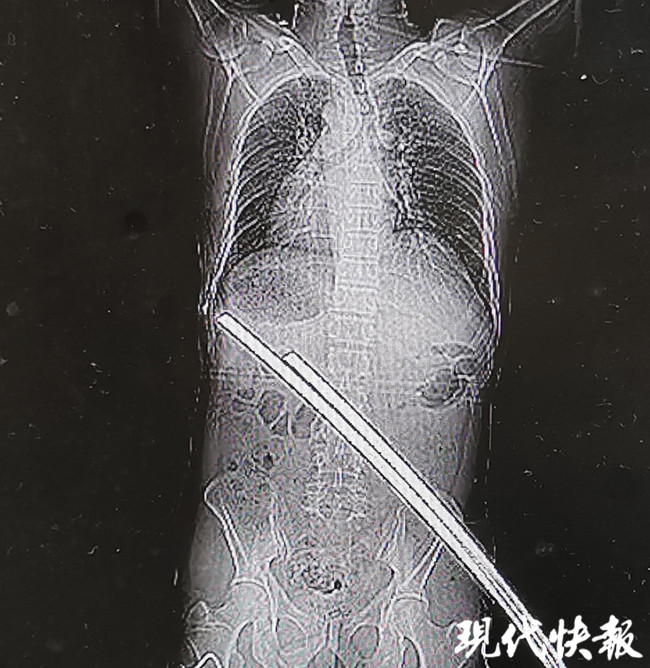

△刺穿張師傅身體的兩根鋼筋

通過CT檢查,醫(yī)生稱鋼筋只是刺穿張師傅的肌肉,萬幸的是并未累及身體重要臟器和血管,除此以外,張師傅肋骨骨折、左肘部皮膚擦傷,無生命危險。經(jīng)過兩個小時的急診手術(shù),鋼筋從張師傅右臀部被拔除,手術(shù)一切順利。